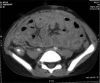

Encapsulating peritoneal sclerosis (EPS) is an infrequent but serious complication of long-term peritoneal dialysis with 50% mortality and lack consensus on treatment. The pathogenesis of EPS is ill understood, and diagnosis lacks specificity and relies on clinical, radiographic and microscopic evaluation. Since there is no general agreement on managing EPS, we report a case treated successfully with surgery followed by immunosuppressive therapy with tamoxifen and steroids. He later successfully underwent deceased donor renal transplantation.